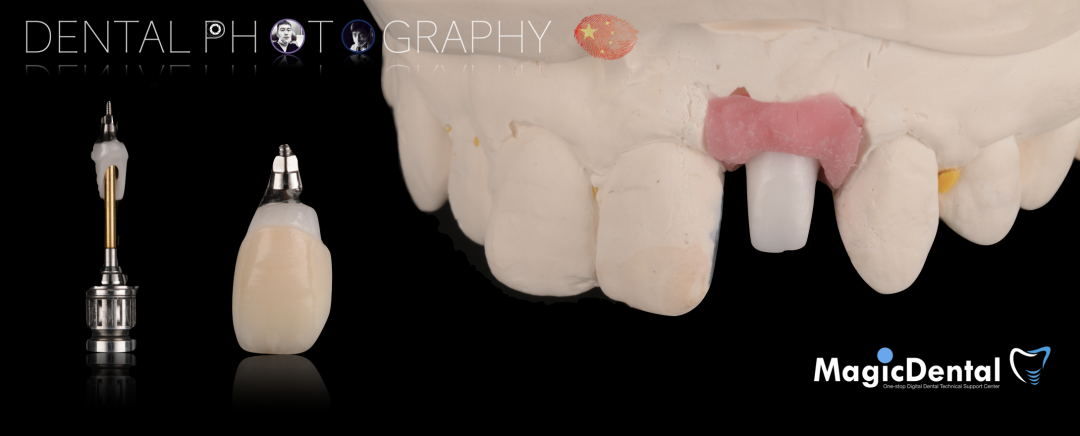

骨块细节

切开翻瓣,彻底暴露术区,试戴骨块。

调整骨块外形,适配受植区域,打开骨髓腔。

预备固位钉洞,固定骨块

骨膜减张,放置骨粉,放置骨块,钛钉固定骨块。

固定骨片,修整骨块边缘,继续放置骨粉覆盖骨块及受植区,放置骨膜,严密缝合创口。